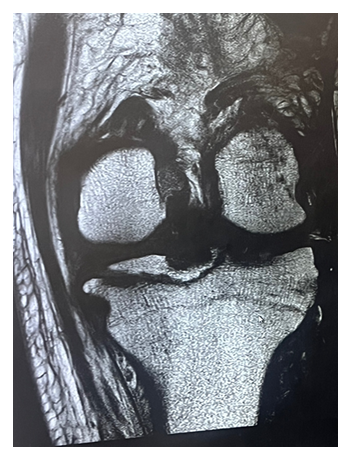

Magnetic resonance imaging revealed a tibial eminence fracture fragment measuring 4.2 cm x 4.4 cm, involving the attachment sites of both the anterior and posterior cruciate ligaments.

Additionally, there was evidence of a complete rupture of the medial collateral ligament. Vascular imaging identified an acute deep venous thrombosis (DVT) in the peroneal vein.